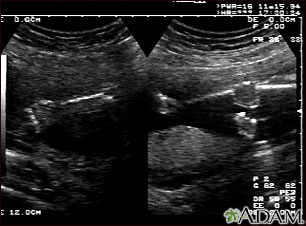

Ultrasound, normal fetus - arms and legs

This is a normal fetal ultrasound performed at 19 weeks gestation. This is the type of spilt-screen display you might see during an ultrasound, or if the technician prints a copy of the ultrasound for you. This ultrasound shows both the left arm (seen in the left side of the display), and the lower extremities (seen in the right side of the display). The white areas of the arm or legs is developing bone.